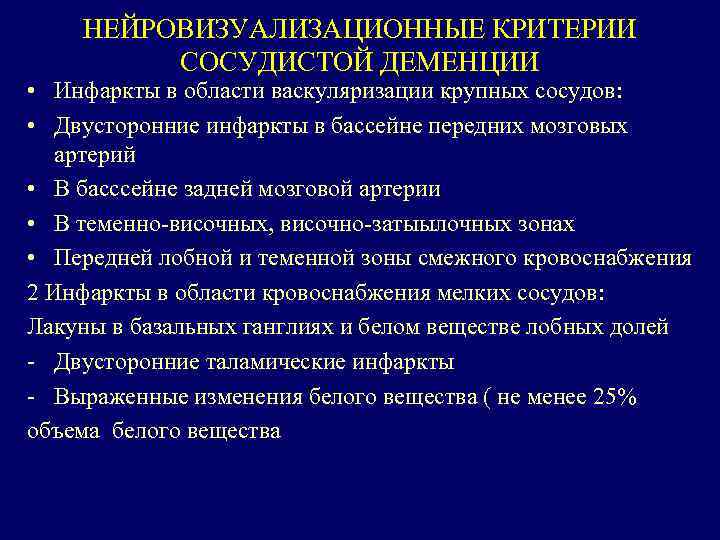

НЕЙРОВИЗУАЛИЗАЦИОННЫЕ КРИТЕРИИ СОСУДИСТОЙ ДЕМЕНЦИИ • Инфаркты в области васкуляризации крупных сосудов: • Двусторонние инфаркты в бассейне передних мозговых артерий • В басссейне задней мозговой артерии • В теменно-височных, височно-затыылочных зонах • Передней лобной и теменной зоны смежного кровоснабжения 2 Инфаркты в области кровоснабжения мелких сосудов: Лакуны в базальных ганглиях и белом веществе лобных долей - Двусторонние таламические инфаркты - Выраженные изменения белого вещества ( не менее 25% объема белого вещества